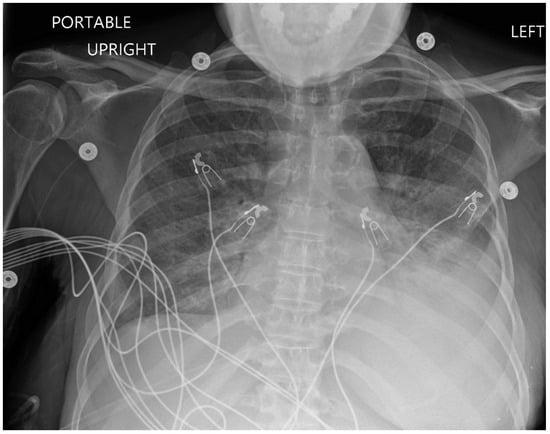

The electrocardiogram (ECG) indicated normal sinus rhythm, with the presence of right axis deviation and left atrial enlargement (Figure 1). The pro-brain natriuretic peptide (BNP) was notably elevated at 17,000. Both rheumatological and immunological evaluations were negative. Infectious disease assessment was notable for reactivity on the Hepatitis B viral panel, while the HIV test returned negative. The chest X-ray revealed pulmonary edema with a left-sided pleural effusion (Figure 2). A computerized tomography (CT) pulmonary angiogram did not show any evidence of pulmonary emboli (PE), but it did indicate diffuse bilateral ground-glass opacities consistent with pulmonary edema, as well as enlargement of the pulmonary arteries and cardiomegaly (Figure 3). Clinical suspicion for pneumonia was deemed unlikely, as there was an absence of an elevated white blood cell count and C-reactive protein.

Figure 2. Chest X-ray showing pulmonary edema with a left-sided pleural effusion.